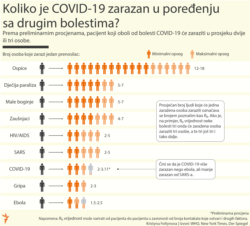

Od pojave korona virusa krajem decembra 2019. u kineskom gradu Vuhanu, 159 zemalja i teritorija širom sveta prijavile su slučajeve obolelih od COVID-19, bolesti koju ovaj virus izaziva.

Širom sveta ima više od 222.000 obolelih. U svim zemljama Zapadnog Balkana ima obolelih a zemlje uvode rigorozne mere ograničenja kretanja kako bi sprečile širenje virusa.